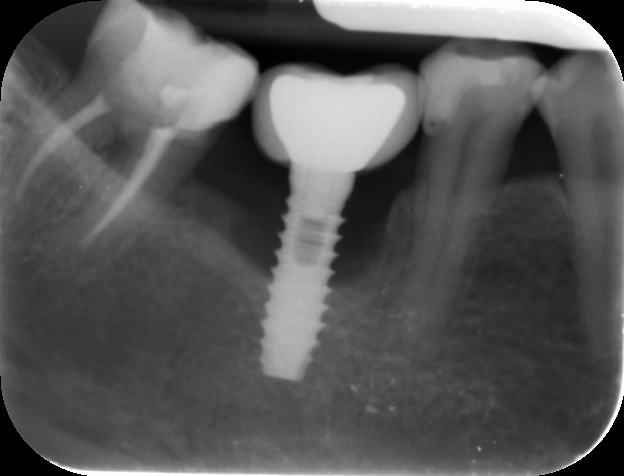

Hola compañeros, acude paciente, con implante en posición 21, colocado hace 15 años, desconocemos marca. Acude por caída de la corona, debido a la fractura del muñon atornillado sobre el [...]

Hola ,tengo un caso de un implante colocado en Venezuela y la paciente viene con el nombre del implante colocado pero no equivale al q tiene en boca ,les mando [...]